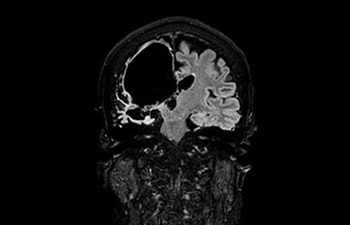

Lesión cerebral

con Compressed SENSE